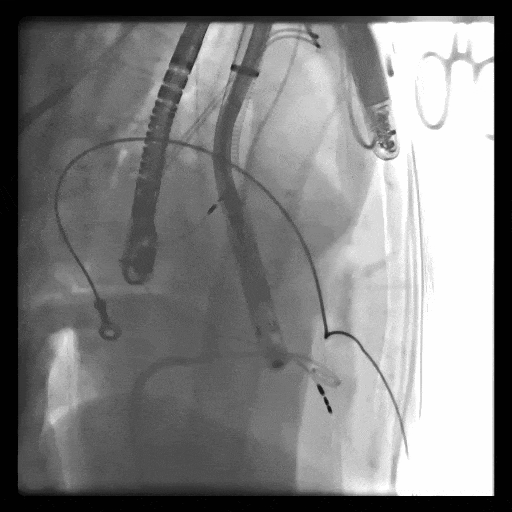

第一例患者手術(shù)難點(diǎn)

1、血管入路問題,最窄處平均徑5.5mm(小于8.5mm),輸送器存在進(jìn)入受阻礙風(fēng)險; 2、投照體位過大,RAO76°,術(shù)中影響輸送器操作可能性大;3、三尖瓣環(huán)大,同軸性難調(diào)整,易產(chǎn)生瓣周漏;4、起搏器導(dǎo)線在三尖瓣瓣環(huán)中心位置穿過,且較短,可能限制人工瓣膜展開,且尖端靠近室間隔錨定區(qū),可能影響錨定;5、三尖瓣極重度反流,藥物不能緩解患者的癥狀,在應(yīng)用LuX-Valve Plus之前,心臟專家經(jīng)長時間評估均未為患者找到合適的產(chǎn)品或治療方案。

術(shù)中DSA顯示起搏器導(dǎo)線的干擾,右心室造影確定瓣環(huán)位置,操作空間小